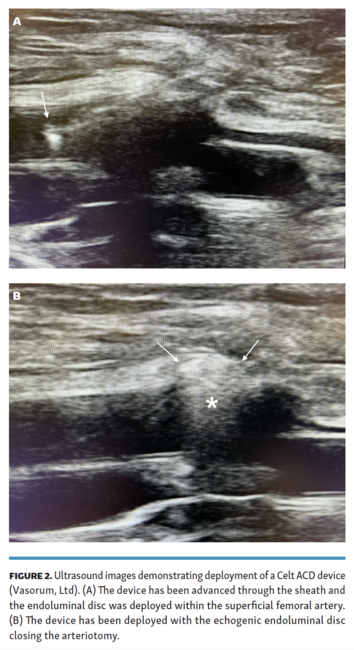

The location of the lesser trochanter was marked with fluoroscopy prior to arterial puncture. All antegrade superficial femoral artery access attempts were performed under real-time ultrasound guidance with a modified Seldinger technique approximately at the level of the lesser trochanter. All patients were administered heparin immediately after access was obtained. Activated clotting times were not routinely monitored throughout cases and no patients had their heparinization reversed. Intravascular ultrasound was utilized for all cases. After ultrasound was used to evaluate the lesion being treated, the catheter was withdrawn and used to measure the superficial femoral artery lumen size at the level of the distal tip of the sheath. At the end of each case, the Celt ACD was deployed per the company’s instructions for use. The device was placed through the pre-existing sheath and the device handle was turned clockwise to deploy the endoluminal disc. The device and sheath were retracted until gentle resistance was met, signaling that the endoluminal disc was apposed to the arterial wall. Good apposition between the endoluminal disc and the arterial wall was then confirmed with ultrasound. The device was then oriented perpendicular to the skin and the device handle was turned counter-clockwise, deploying the second disc on the exterior of the artery. The device lever was then pulled, which detaches the arteriotomy closure clip from the device, and the device was removed. The access site was then inspected for bleeding and palpated to evaluate for hematoma. Examples of intraprocedural ultrasound and fluoroscopy images are shown in Figure 2 and Figure 3.